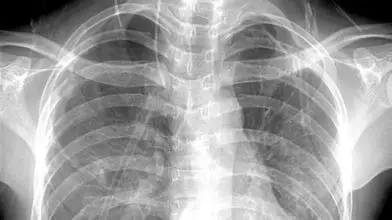

X线

像把面包压扁了看

X线会穿过人体,遇到被遮挡的部位,底片上不会曝光,洗片后这个部位就是白色的。

就像一片面包或一块棉花,看不到里面的纤维纹理,但用手压瘪了会清晰一些。

X线最大缺点是受制于深浅组织的影像相互重叠和隐藏,有时需要多次多角度拍摄X线片。

外伤骨头——粗看X线片,细看CT,核磁看不清

各种外伤,如果怀疑伤到了骨头,优先选择X光照片,检查结果快速易得。若要进一步观察,可以选择CT。超声、核磁对于骨皮髓质等看不大清,一般不选择。

3 胸部——粗看X线片,细看CT,看肺不要选核磁

X线胸片可粗略检查心脏、主动脉、肺、胸膜、肋骨等,可以检查有无肺纹理增多、肺部钙化点、主动脉结钙化等。

胸部CT检查显示出的结构更清晰,对胸部病变检出敏感性和显示病变的准确性均优于常规X线胸片,特别是对于早期肺癌确诊有决定性意义。

但是CT检查的辐射剂量高于X线,核磁对于肺部疾病的诊断,应用非常有限。